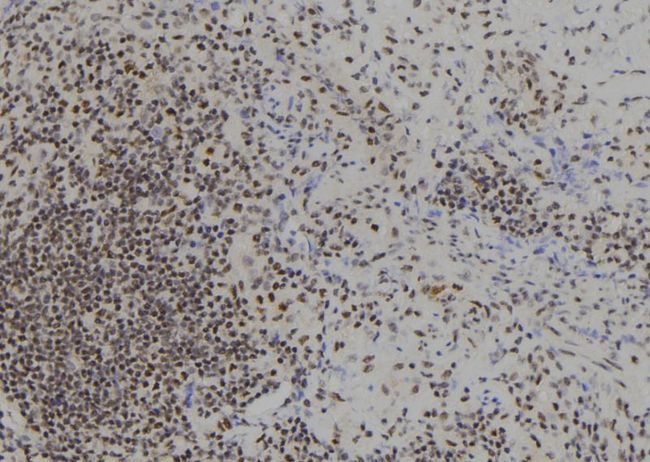

- Main image

- Experimental details

- 1:100 staining human spleen tissue by IHC-P. The sample was formaldehyde fixed and a heat mediated antigen retrieval step in citrate buffer was performed. The sample was then blocked and incubated with the antibody for 1.5 hours at 22°C. An HRP conjugated goat anti-rabbit antibody was used as the secondary.